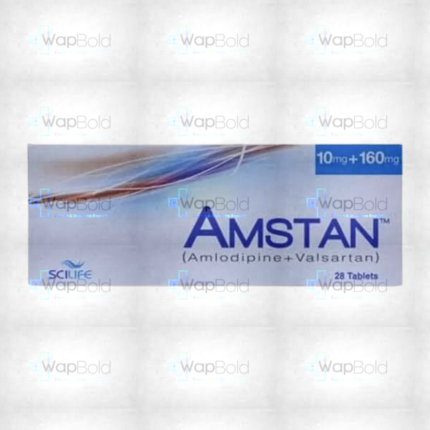

Amstan Tablets 10/160Mg (1 Box = 1 Strip)(1 Strip = 14 Tablets)